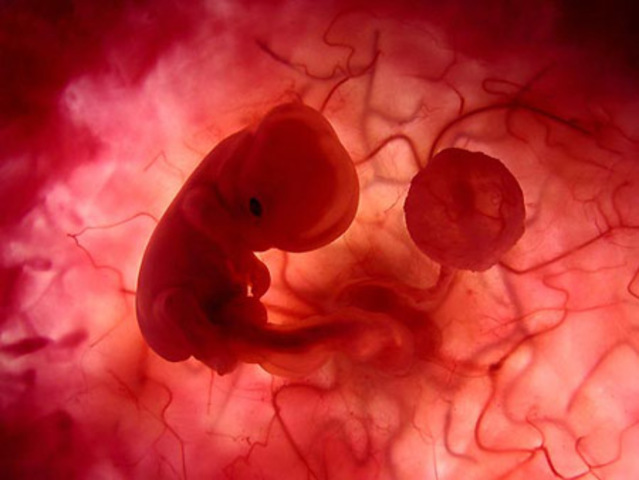

• 4ta Semana de Gestación

4ta Semana de Gestación

El tubo neural del embrión esta terminando de cerrarse y solo se pueden ver los neuroporos craneal y caudal el craneal se cierra el día 25 despúes de la fertilizaión y el caudal dos días despúes.

• Period: to

4ta SDG

En la región externa de la cabeza se ven las placodas(engrosamiento de ectodermo) dorsal y lateralmente estan las placodas óticas que originan el oido interno, en la región ventral y lateral estan las placodas ópticas que forman el crsitalino , a los lados de la línea media las placodas nasales que desarrollarán la nariz, en el cuello se forman 3 pares de arcos faringeos que dan las estructuras del cuello y cara , por fuera se localiza el corazón , la cresta ectodérmica da origen a extremidades